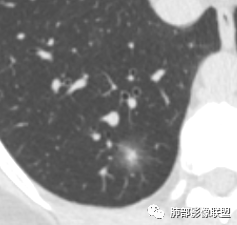

连续层面显示这个应该是空泡,或者小空洞,远端没有,近端也没有,周围环形软组织增厚。而空泡,影像上只是根据5mm界线,病理上不一定。

这些呢?为啥?

动脉,有支气管伴行

伴有支气管

南边:

假如这是含气支气管,伴随的哪条动脉呢?近端从哪来?为啥环形壁增厚而又不均匀?都不太符合,所以支持空泡或小空洞。

上次刘纯老师提出,空泡征是一个影像征象,不是一个病理征象,我比较支持,他就是一个影像上的小低密度腔,原因很多,但是影像上与小的空洞表现区分不了。其中的原理:有一条是内容物排出后的残腔,其实也是空洞的原理。